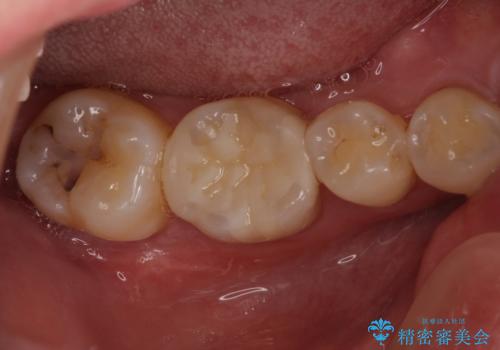

古い材料も虫歯もすべて除去して、根本からやりかえました。

セラミックが欠けるほど強い力がかかっているということは、ご自身の歯も割れている(小さいヒビ等も含む)可能性があります。拡大鏡でしっかり見ながら治療します。

咬む力が強いため、このままでは何度もセラミックとご自身の歯を割る可能性就寝時マウスピースの使用をご提案しました。患者様には、大変満足して頂きました。